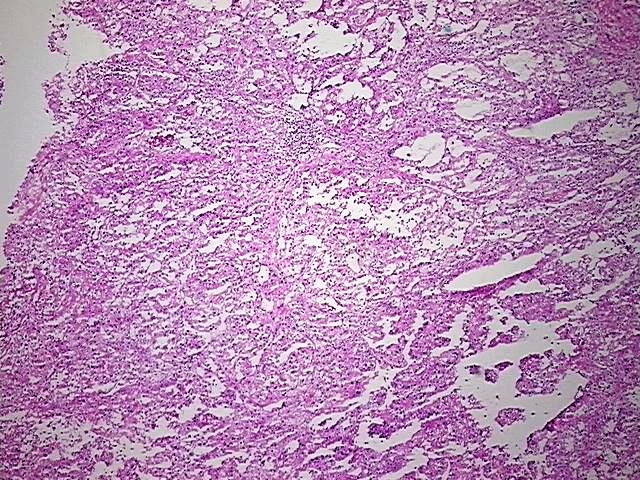

DNA - 4x.

Tissue Genomic DNA, Kidney

- Scientific DescriptionDNA (5 microg); Kidney; Carcinoma of kidney, renal cell, chromophil, papillary